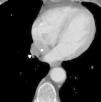

A 75-year-old woman diagnosed with a pharyngeal cancer was referred for magnetic resonance imaging of the neck and a computed tomography (CT) of the chest and upper abdomen. The enhanced CT chest demonstrated an incidental tubular cystic lesion, oriented parallel to the mediastinum, within the right pulmonary ligament, extending from the level just caudal to the right inferior pulmonary vein down to the diaphragm. This lesion measured 5.5cm×2.7cm×1.8cm and showed homogeneous density, mean attenuation value=−3.92Hounsfield Units (HU). This lesion was separated from pericardium by a layer of fat. The lesion was followed up and remained stable in size and shape for 4 years, as per the comparison with a previous CT scan. The appearance on axial, coronal and sagittal planes confirmed that the cyst was within the pulmonary ligament (Figs. 1 and 2). The cystic lesion also had no depression of the hilar structures or elevation or blurring of the diaphragm. So the non-symptomatic clinical setting alongside with the anatomical landmarks described and the lack of change in size/configuration during these years supported the diagnosis of a mesothelial cyst of the pulmonary ligament.